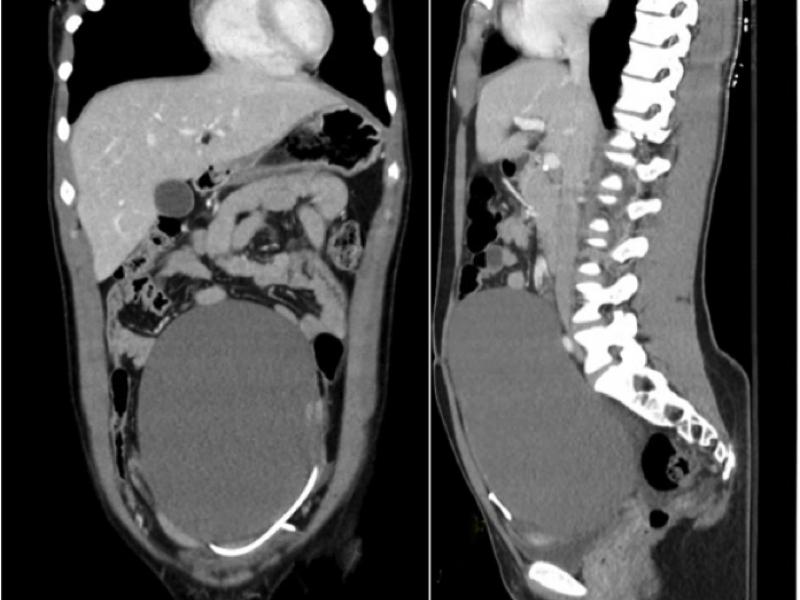

A 25 yo female presents with abdominal pain and associated